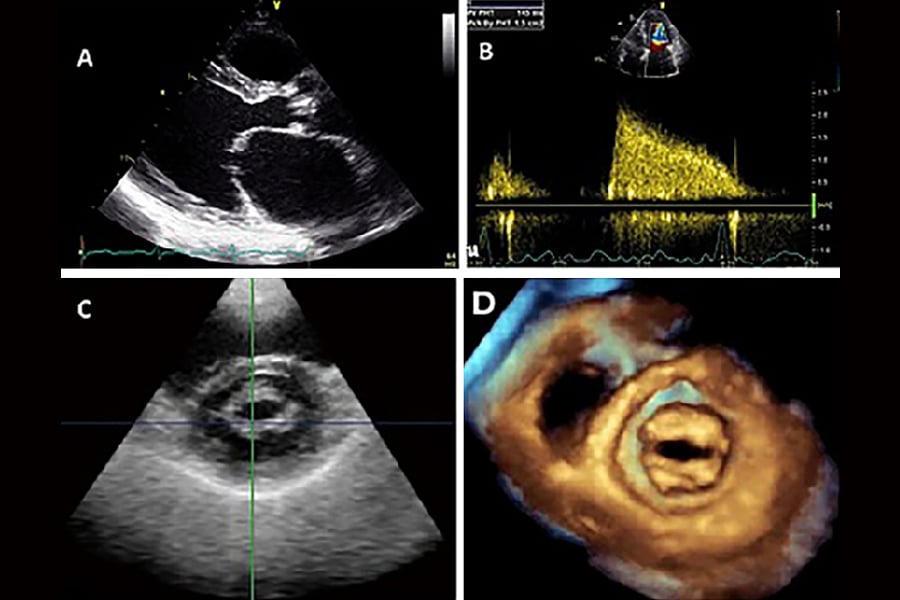

- اکوکاردیوگرام (اکو). این آزمایش غیرتهاجمی از امواج صوتی برای ارزیابی حفرهها و دریچههای قلب استفاده میکند. امواج صوتی اکو، تصویری را بر روی مانیتور ایجاد میکنند که مبدل اولتراسوند از روی قلب عبور میکند. این بهترین آزمایش برای ارزیابی عملکرد دریچه قلب است.

- اکوکاردیوگرافی مری (TEE) . این تست شامل عبور دادن یک مبدل اولتراسوند کوچک به مری است. امواج صوتی، تصویری از دریچهها و حفرههای قلب روی مانیتور کامپیوتر ایجاد میکنند بدون اینکه دندهها یا ریهها مانع شوند.